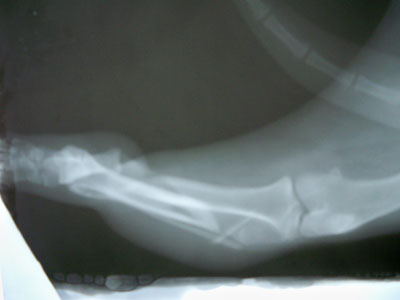

Μεσαίου μεγέθους 1-2 ετών με λοξό τέλειο κάταγμα στο άνω / 3 της διάφυσης της αριστερής κνήμης. Πραγματοποιήθηκε χειρουργική επέμβαση στις 01/10/09. Τοποθετήθηκε μεταλλική πλάκα στην έσω επιφάνεια της κνήμης με 6 κοχλίες και συμπιεστικός κοχλίας εγκάρσια στην καταγματική γραμμή. Το ζώο βρίσκεται υπό περιορισμό.Η αποκατάσταση ήταν 100 % και τα υλικά αφαιρέθηκαν 7 μήνες μετά .